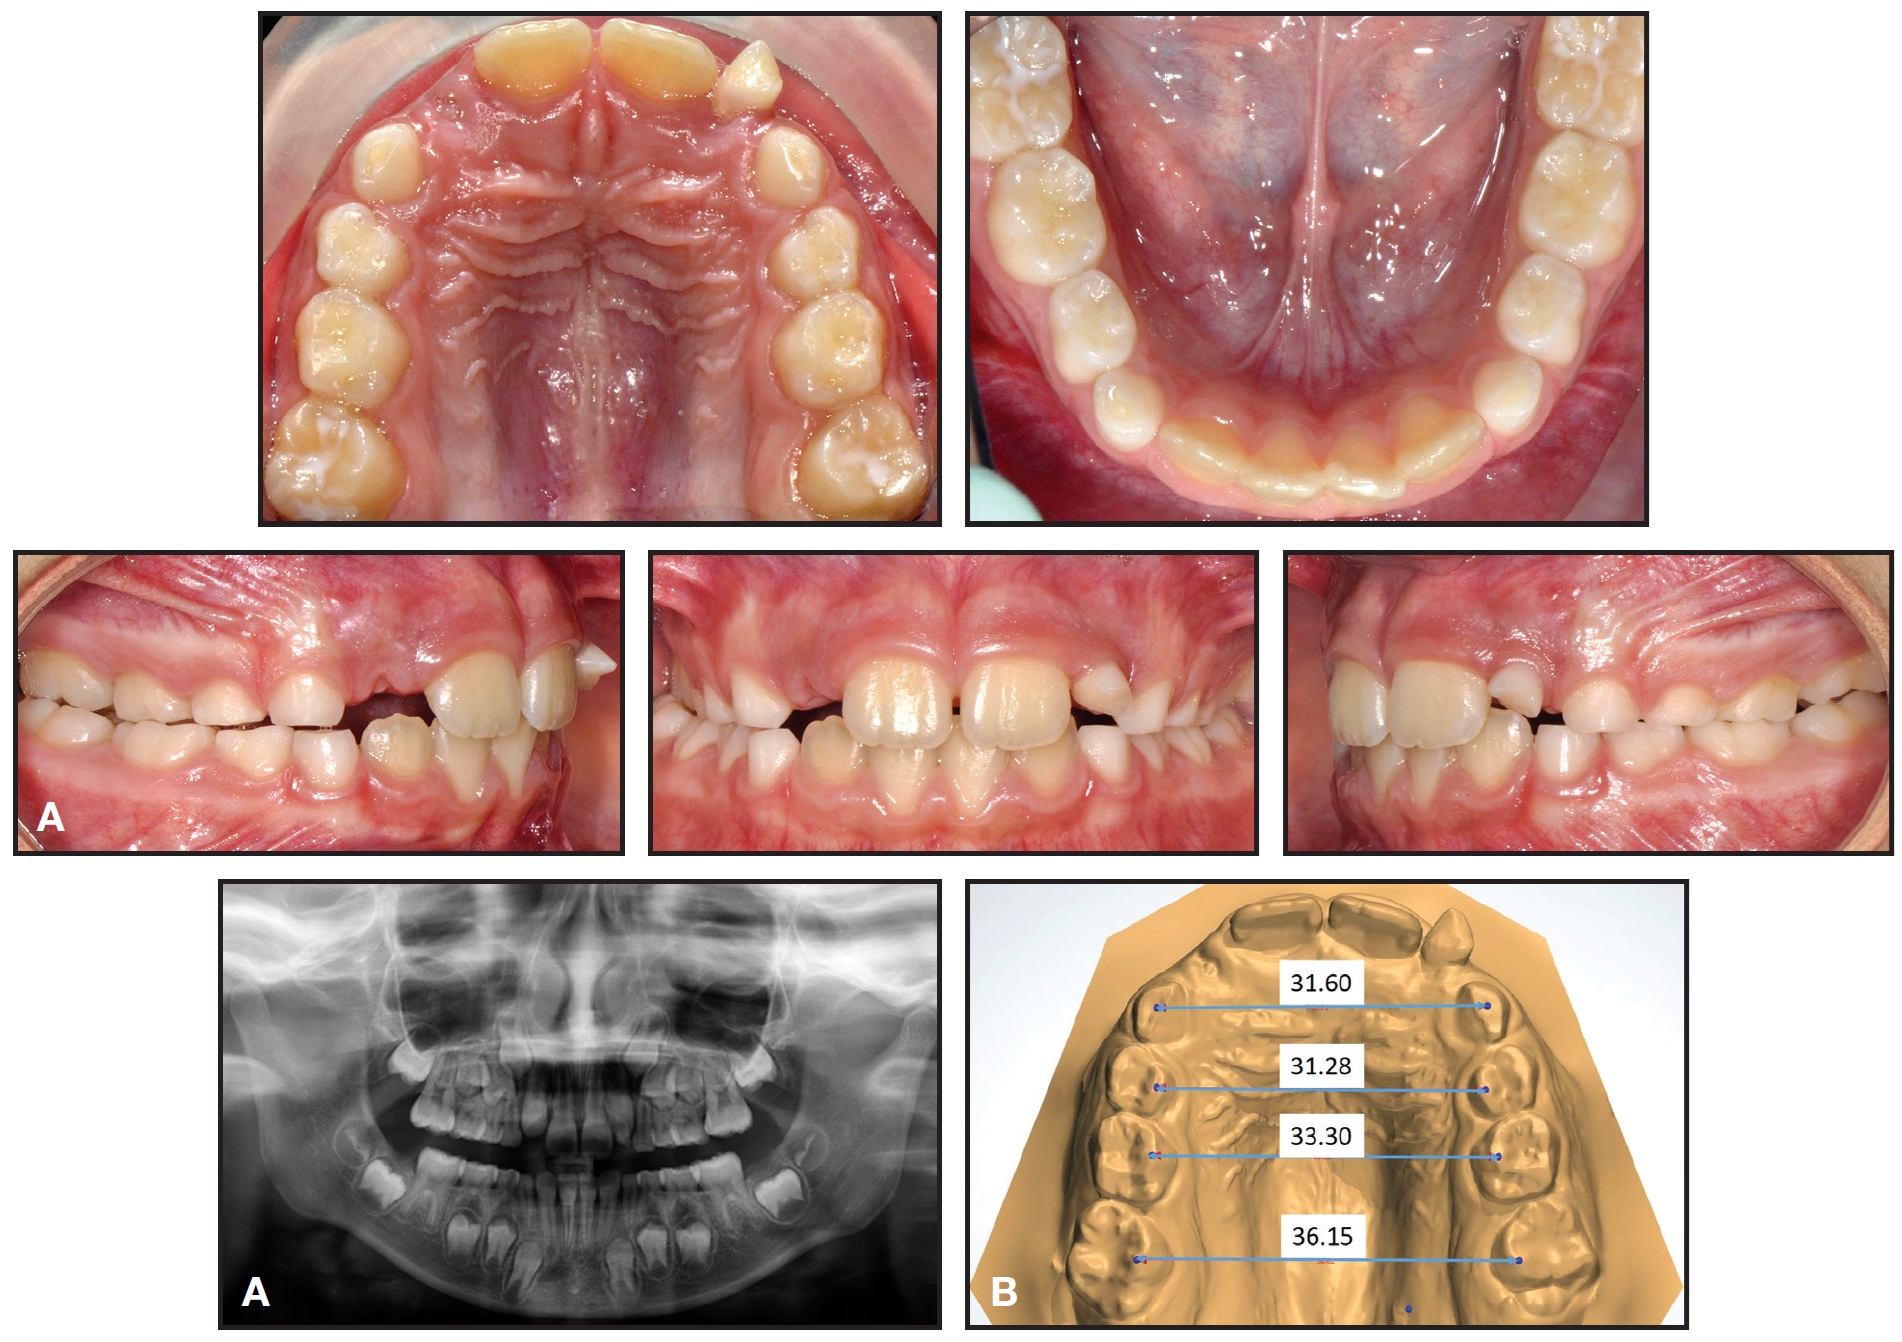

A 7-year-old female in the mixed dentition presented with a crossbite associated with a right lateral deviation of the mandible and a transverse deficiency (Fig. 8).

Fig. 8 Case 2. A. 7-year-old female patient with maxillary transverse deficiency, crossbite, and mandibular deviation before treatment. B. Arch-width measurements (mm) on STL digital casts obtained from intraoral scan.

A Leaf Expander was bonded to bands on the second deciduous molars, with extensions to the canines and first deciduous molars (Fig. 9A).

The screw was reactivated over the next six months to obtain 6mm of expansion (Fig. 9B).

Fig. 9 Case 2. A. Leaf Expander in place. B. After six months of expansion.

After another three months of retention, the appliance was removed. Final records confirmed that the crossbite and midline deviation were corrected; the maxilla was expanded enough for eruption of the upper lateral incisors; and the first permanent molars had spontaneously expanded and rotated (Fig. 10, Table 2). Treatment results were stable nine months later (Fig. 11).

Fig. 10 Case 2. A. After three months of retention (images obtained from intraoral scan). B. Superimposition of pre- and post-treatment results on palatal rugae.